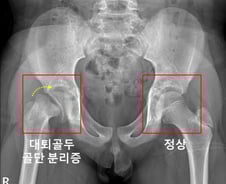

허벅지뼈(대퇴골)의 윗부분을 대퇴골두라 한다. 외상을 입지 않았는데도 대퇴골두가 분리되는 질환이 '대퇴골두 골단 분리증'이다. 주요 원인으로 내분비질환이 꼽히는데, 내분비질환을 앓는 소아청소년 환자에서의 대퇴골두 골단 분리증의 발병률을 한국 연구진이 세계 최초로 규명했다. 서울대어린이병원 신창호 교수·이윤정 교수 공동 연구팀(황성현 전문의)은 국민건강보험공단 데이터를 활용해 내분비질환 환자 8만769명과 대퇴골두 골단 분리증 환자 191명을 14년간 추적 관찰한 결과를 20일 발표했다. 허벅지뼈(대퇴골) 위쪽의 성장판 부위에서 대퇴골두와 그 아래 뼈가 특별한 외상이 없는 데도 분리될 때 대퇴골두 골단 분리증으로 진단한다. 진단이 늦어지면 대퇴비구 충돌증후군, 대퇴골두가 썩는 대퇴골두 무혈성 괴사가 발생할 수 있다. 대퇴골두 골단 분리증의 주요 위험 요인으로 '내분비질환'이 꼽힌다. 하지만 기존 연구들에서는 각 내분비질환에 따라 실제 위험도가 얼마나 되는지, 부족한 호르몬 개수에 따